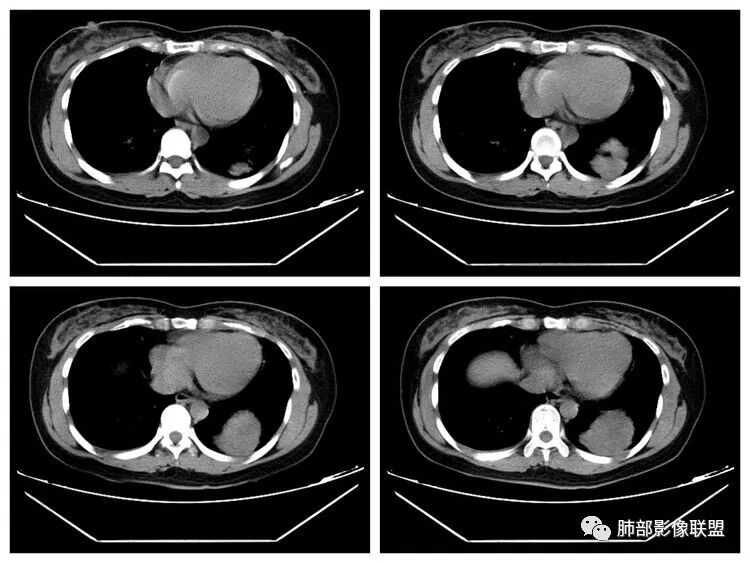

下面看第三部分了,3月20日补增强扫描:

M-Imaging :错了,这么大,膈肌后方南边:定位?定性?Shelia:肺外。感觉病灶是个扁平状,虽然没有蛇纹血管征,但是延迟强化,怀疑纤维来源,考虑sft

M-Imaging :肿块与胸膜夹角是锐角,有分叶,觉得肺内Lotus:mpr重建再看一下南边:与支气管有关系吗Shelia:没有关系。与胸膜分不清

南边:

宇宙星空:没有关系。长轴与胸膜平行吧?

Coke with ice:与肺韧带有关系。与肺韧带的夹角呈钝角,感觉有胸膜尾

宇宙星空:糊墙关系:

南边:边缘这么光滑,无分叶,与胸膜关系密切

D字征

首先良性,倾向于SFT,不除外PSP

小微:肺外肿瘤

宇宙星空:延迟明显强化,其内可见条索状低密度,支持SFT

lmg:其内可见血管穿行吧,考虑SFT

一米阳光:与膈胸膜关系密切,肺受压。考虑SFT

远方: